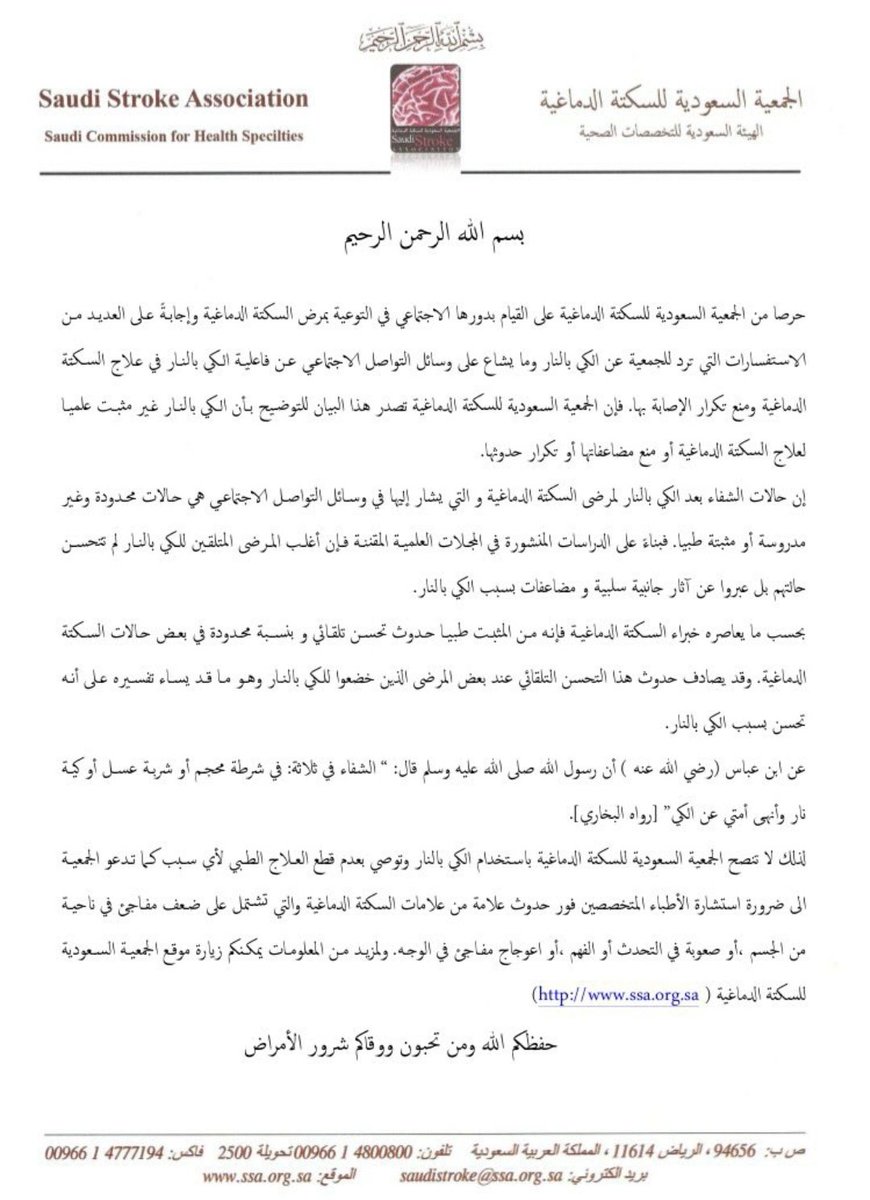

بما يخص #الكي كعلاج السكته الدماغيه

🧠لا ننصح🧠

كأطباء اعصاب به

♦️لعدم وجود دراسات اثبتت جدواه

♦️لاننا لاحظنا وجود مضاعفات منه كالالتهابات والتشوهات المصاحبه

وقد صدر بيان من الجمعيه السعوديه للسكته الدماغيه بالمملكة بذلك @stroke_org_sa

🧠لا ننصح🧠

كأطباء اعصاب به

♦️لعدم وجود دراسات اثبتت جدواه

♦️لاننا لاحظنا وجود مضاعفات منه كالالتهابات والتشوهات المصاحبه

وقد صدر بيان من الجمعيه السعوديه للسكته الدماغيه بالمملكة بذلك @stroke_org_sa